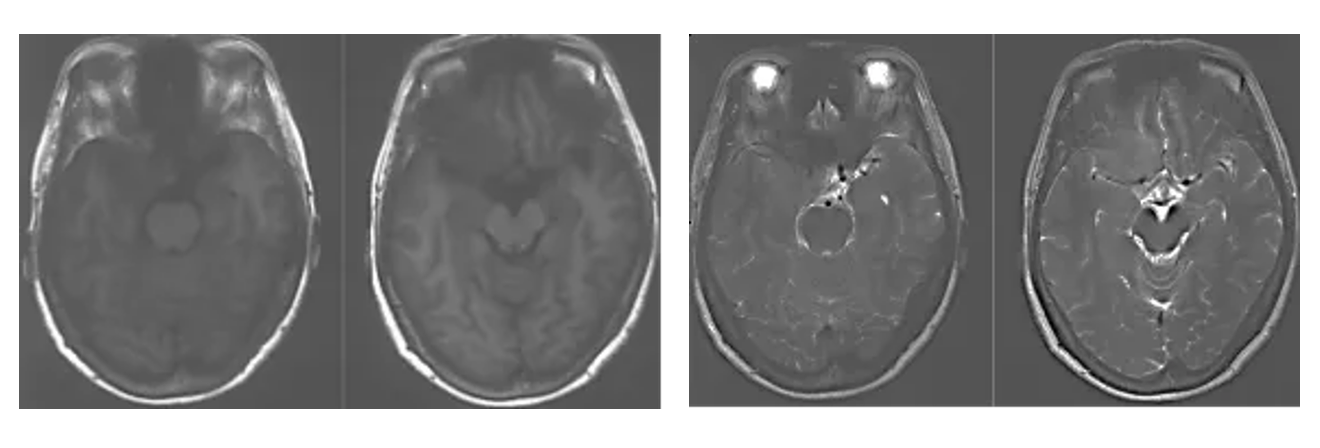

Cranial MRI enhanced

1. MRI T1 and T2 images showed a solid tumor in the medial region of the right sphenoid crest with long T1 and short T2 signals, and peritumoral edema was not obvious.

2. Enhanced axial, coronal and sagittal positions showed that the tumor strengthened uniformly with a broad base, mainly located in the medial part of the right sphenoid crest, the base of middle cranial fossa, the saddle diaphragm, encroaching on the cavernous sinus bilaterally, and the internal carotid artery, the middle cerebral artery and the anterior cerebral artery and their perforating blood vessels were encircled by the tumor.